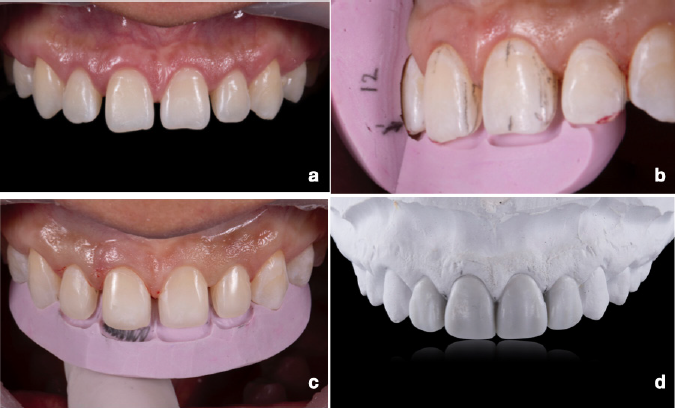

A los 90 días de cicatrización (Figura 2. a) se tomó la impresión con polivinil siloxano de cada arcada para producir un modelo de estudio con yeso tipo IV (Super Rock, Kuraray Noritake Dental Inc., Okayama, Japón). Se seleccionó el polivinil siloxano porque ofrece estabilidad y la posibilidad de obtener más de un modelo con igual precisión a partir de la misma impresión. Enseguida se realizó un montaje cruzado con el nuevo modelo y el montaje previo, y se realizó un encerado aditivo con las características de la arquitectura gingival real y dientes ideales con forma triangular.

Figura 2 Inicio de la rehabilitación. a. Cicatrización del alargamiento de corona. b y c. Guías de tallado. d. Encerado de diagnóstico.

Se presentó el encerado a la paciente y al dar su aprobación, se realizó el mock-up. El modelo se sumergió en agua jabonosa por 30 minutos y se realizó la llave de silicón con PVS en técnica putty-wash de doble intensión, se aplicó resina bisacrílica (3MTM ProtempTM 4, 3M Espe Deutschland GmbH, Alemania) para el mock-up sin grabado ácido y se retiraron excedentes de resina. De ahí se evaluó la estética, posición de los bordes incisales en reposo y su aproximación con las antagonistas en los fonemas “S”, así como la exposición dental en reposo y sonriendo para determinar la correcta ubicación de la curva de sonrisa. Este caso no requirió modificación y la paciente aceptó el plan de tratamiento con carillas cerámicas de feldespato.

Existen dos técnicas para las preparaciones de carillas: las guiadas por las superficies dentales existentes y las guiadas por el volumen final previsto por el encerado. En nuestro caso, se desarrollaron guías de tallado axiales, coronales e incisales (Figura 2. b-d), planeando una inserción horizontal. Solo se realizó contorneo de ángulos inciso-proximales con discos Snap-on de diamante para preservar la mayor estructura del esmalte y obtener un espacio de 1 mm con base al encerado, dejando una cara convergente hacia palatino. Lo anterior permite un enfoque ultraconservador y duradero19, dado que no se modifica la longitud del borde incisal del diente natural debido a que se harán más largos. Durante el tallado se presentaron las llaves de silicona para realizar la ameloplastía en los lugares estrictamente necesarios y preservar la mayor estructura posible del esmalte. Todos los dientes involucrados en el tratamiento se prepararon con la misma técnica y con aislamiento relativo.